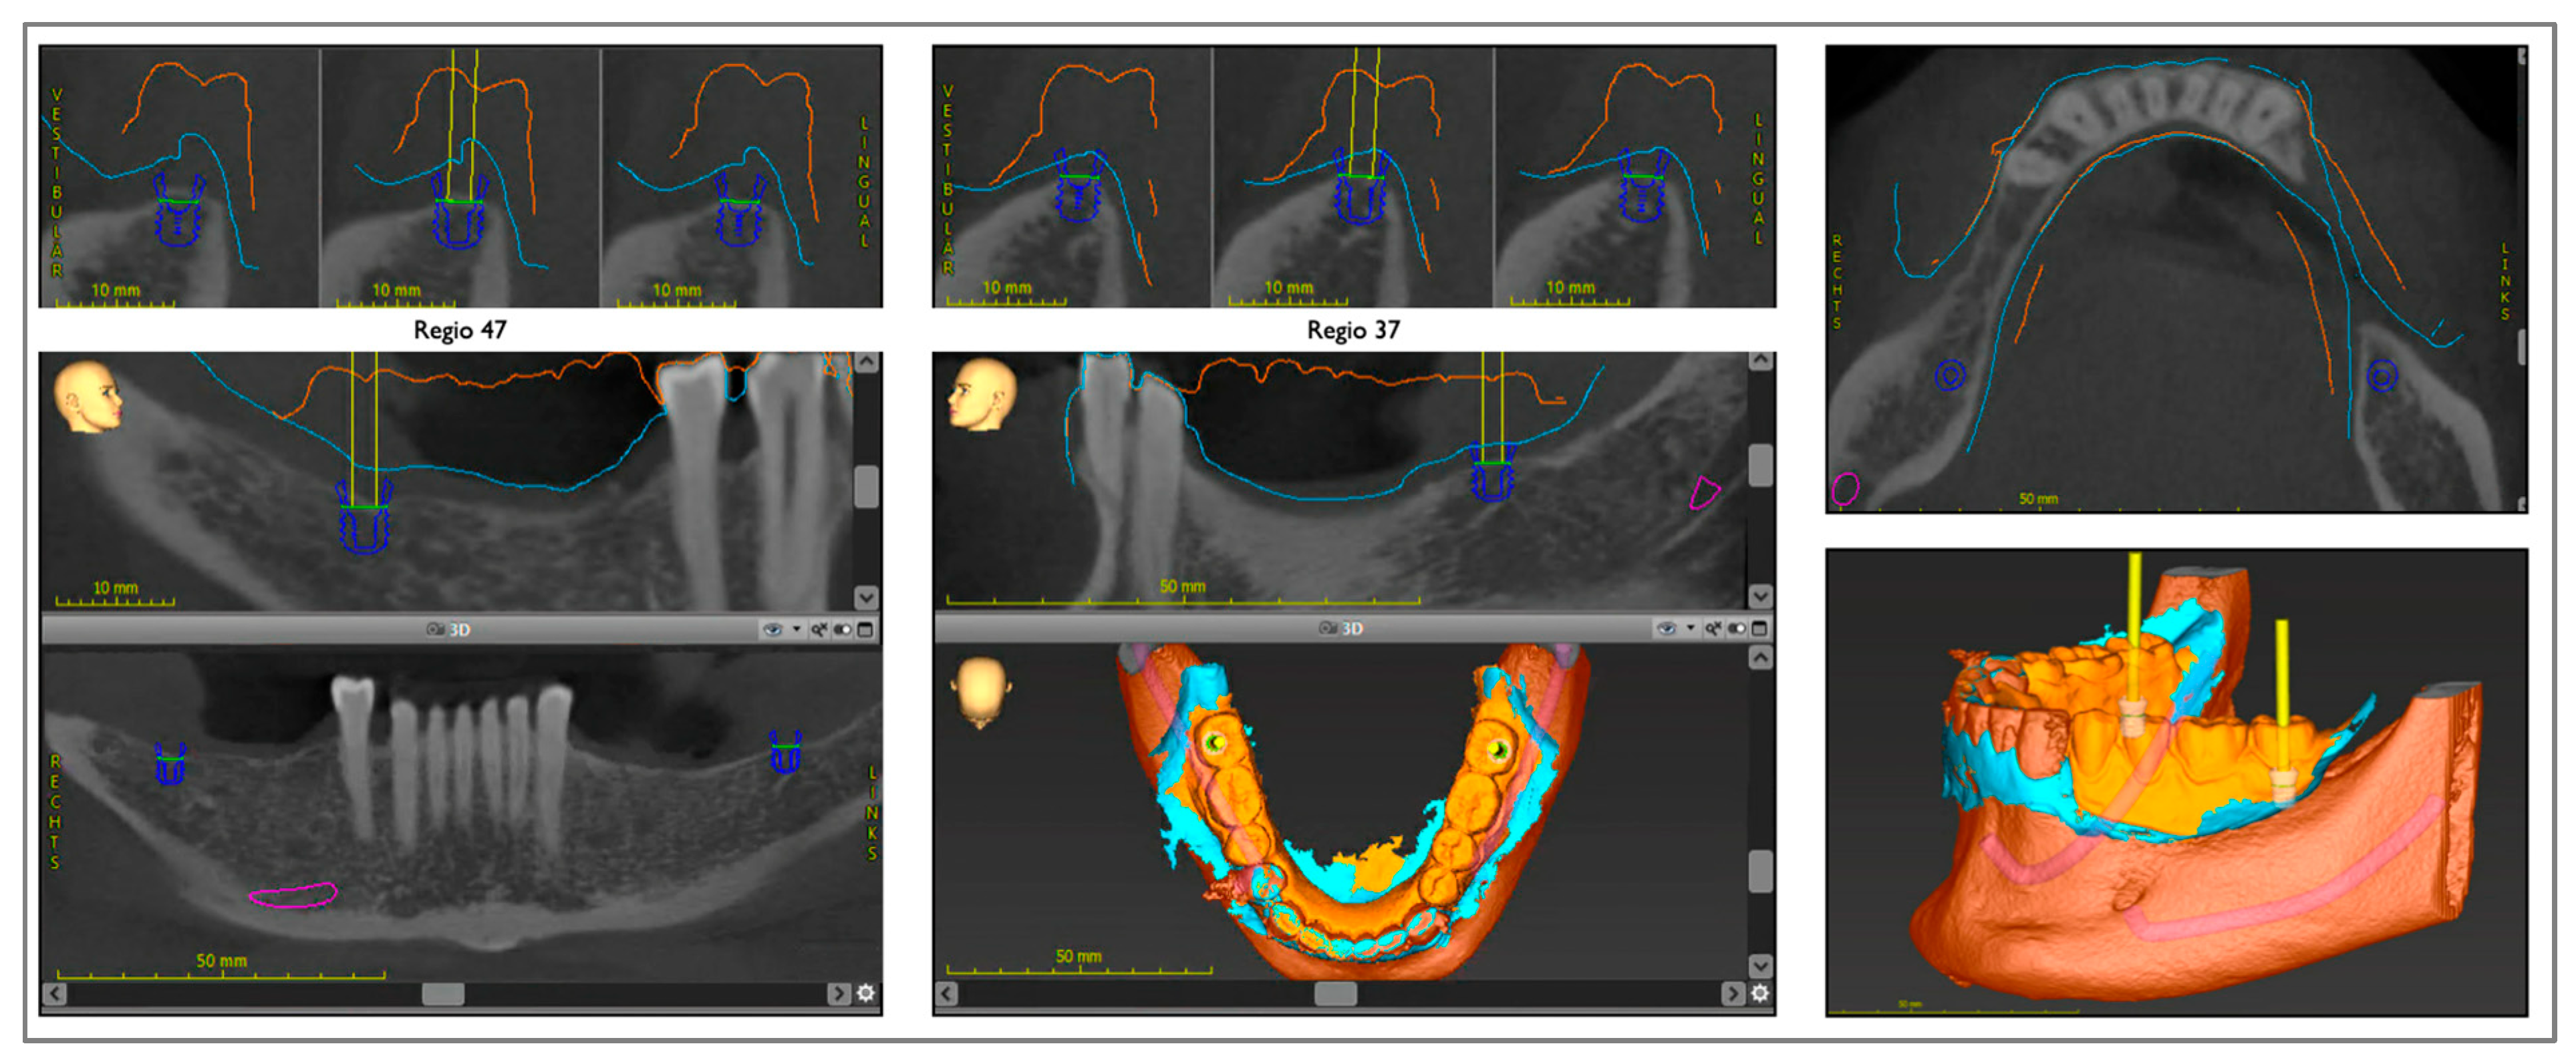

At the same time, two implants were planned using the coDiagnostiX® software (Version 10.7.0, Straumann AG, Basel, Switzerland). Therefore, the intraoral scan of the analog tooth set-up (Figure 3) or a virtual set-up of the previously planned denture design were imported for orientation. This scan of the set-up and the intraoral scan of the mandible without set-up were overlaid with the CBCT data (Figure 3). By switching between the prosthetic planning software (3Shape Dental Manager, version 2.21.2.2 (2021-1), Copenhagen, Denmark) and the implant planning software (coDiagnostiX®, Straumann AG, Basel, Switzerland), the implant axes and positions were aligned according to the path of insertion of the RPD, and the housings in the virtual RPD were planned accordingly. Subsequently, the surgical guide for navigated implant placement was fabricated by 3D printing (Rapidshape P-Series, Straumann AG; Basel, Switzerland).

Figure 3. Digital planning of implants in the second molar region.